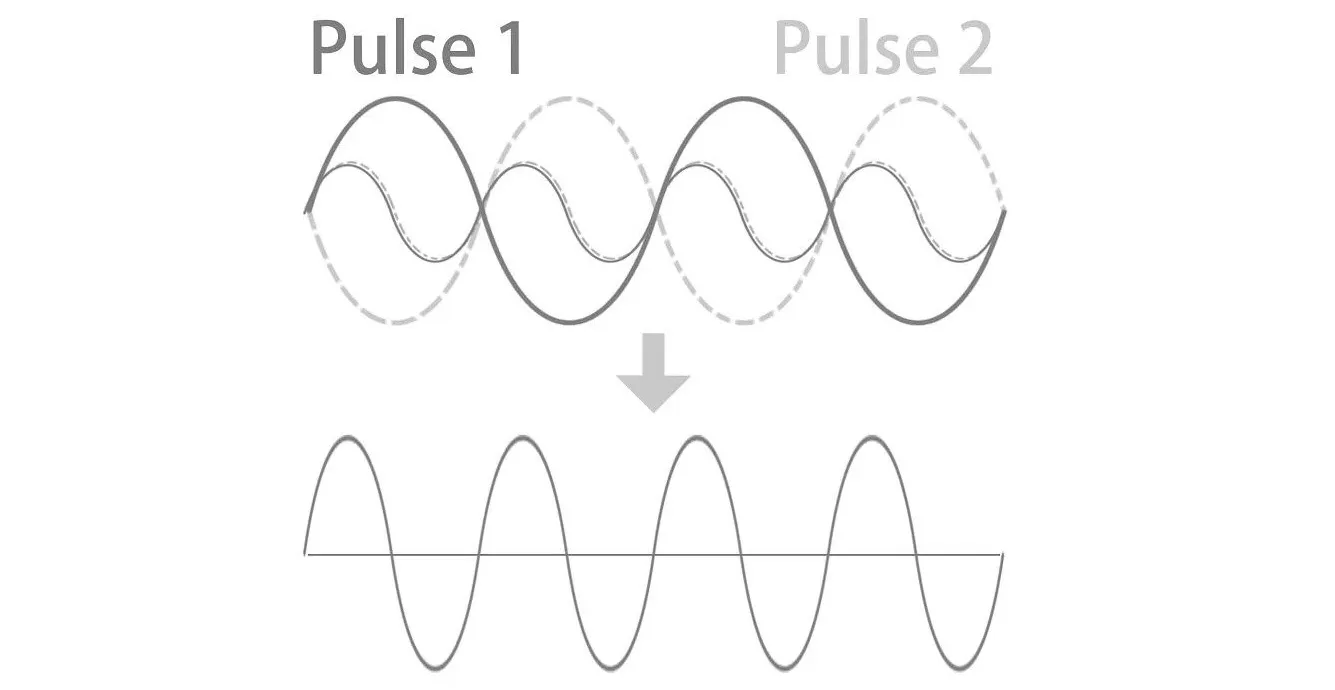

Pulse Inverse Harmonic Imaging (PIHI)

Тканевая инверсная (пульсинверсная) гармоника - технология выделения гармонической составляющей колебаний внутренних органов, вызванных прохождением сквозь тело базового и инверсного ультразвуковых импульсов. Полезным считается сигнал, полученный в результате сложения базовой и инверсной составляющих отраженного сигнала. Технология снижает искажения, создаваемые основной волной, и значительно улучшает отношение сигнал/шум.